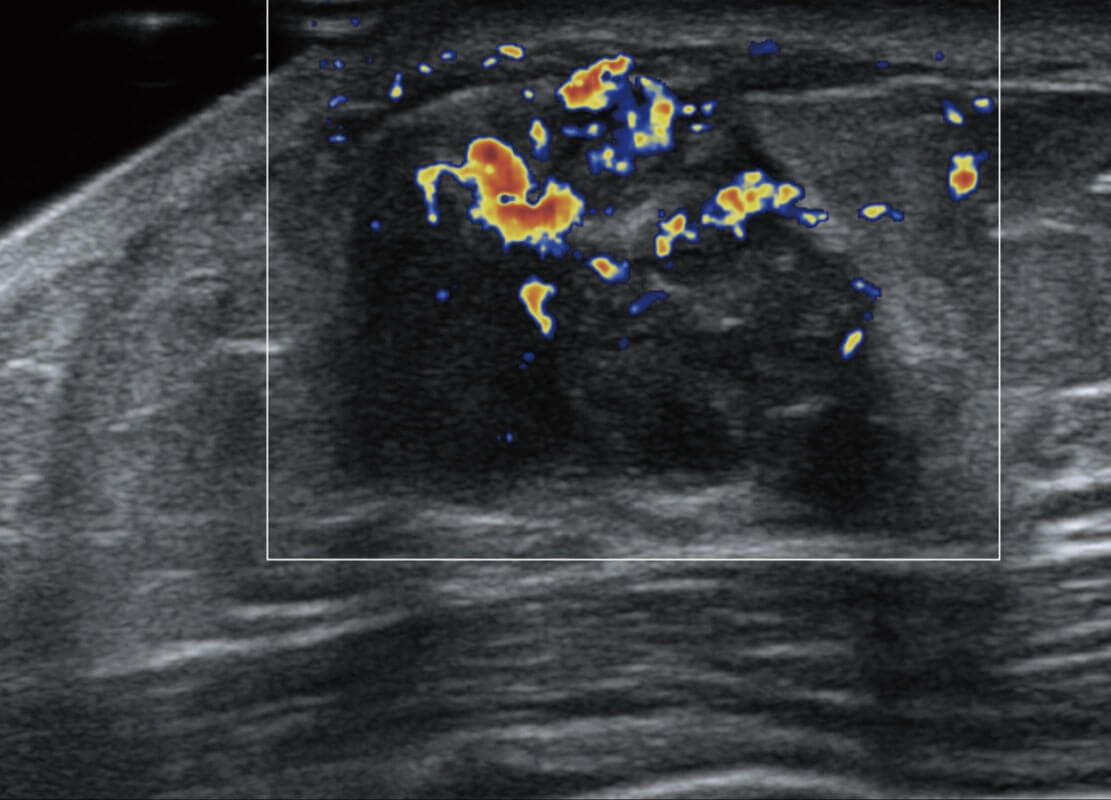

腔内妇科-卵巢

P60优异的图像质量搭载专科探头,在妇科基础疾病的诊断、卵泡生长的监测、输卵管通畅情况的判别等方面为您提供生殖应用方案。